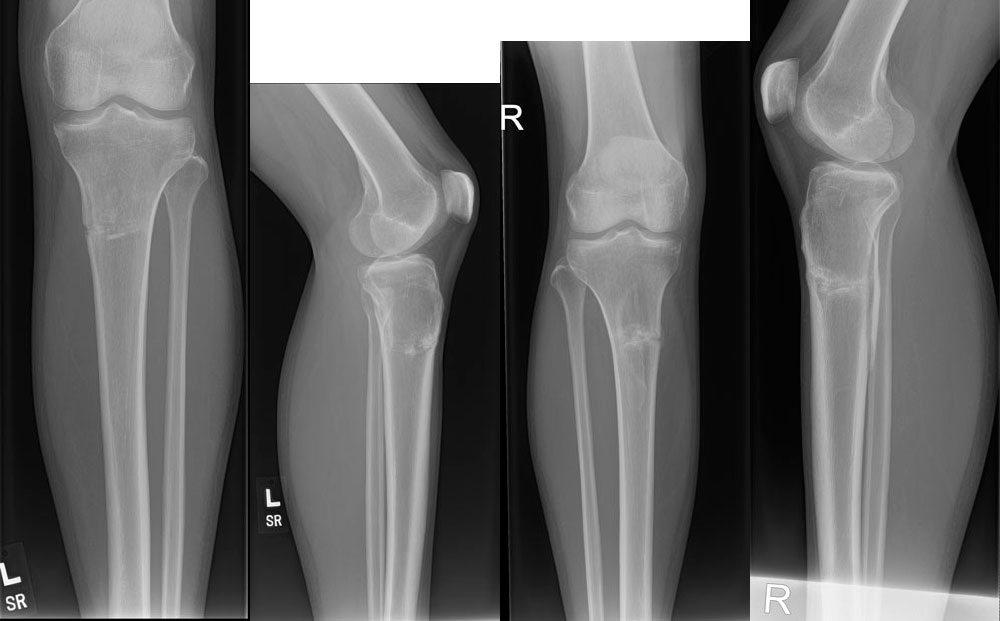

Дата операции 08.09.2017г.

Дата снятия аппаратов 29.11.2017г.

Срок лечения 81 день.

2 месяца с момента снятия аппаратов.

В приложении снимки обеих ног в двух проекциях. Передаю похвальные отзывы от американского мед. персонала.

Здравствуйте, Д.! Рады Вас слышать и особенно оценку Американских коллег.

Рентген отличный! Можно все, без ограничений, каблуки. Только беременность через 6 месяцев.